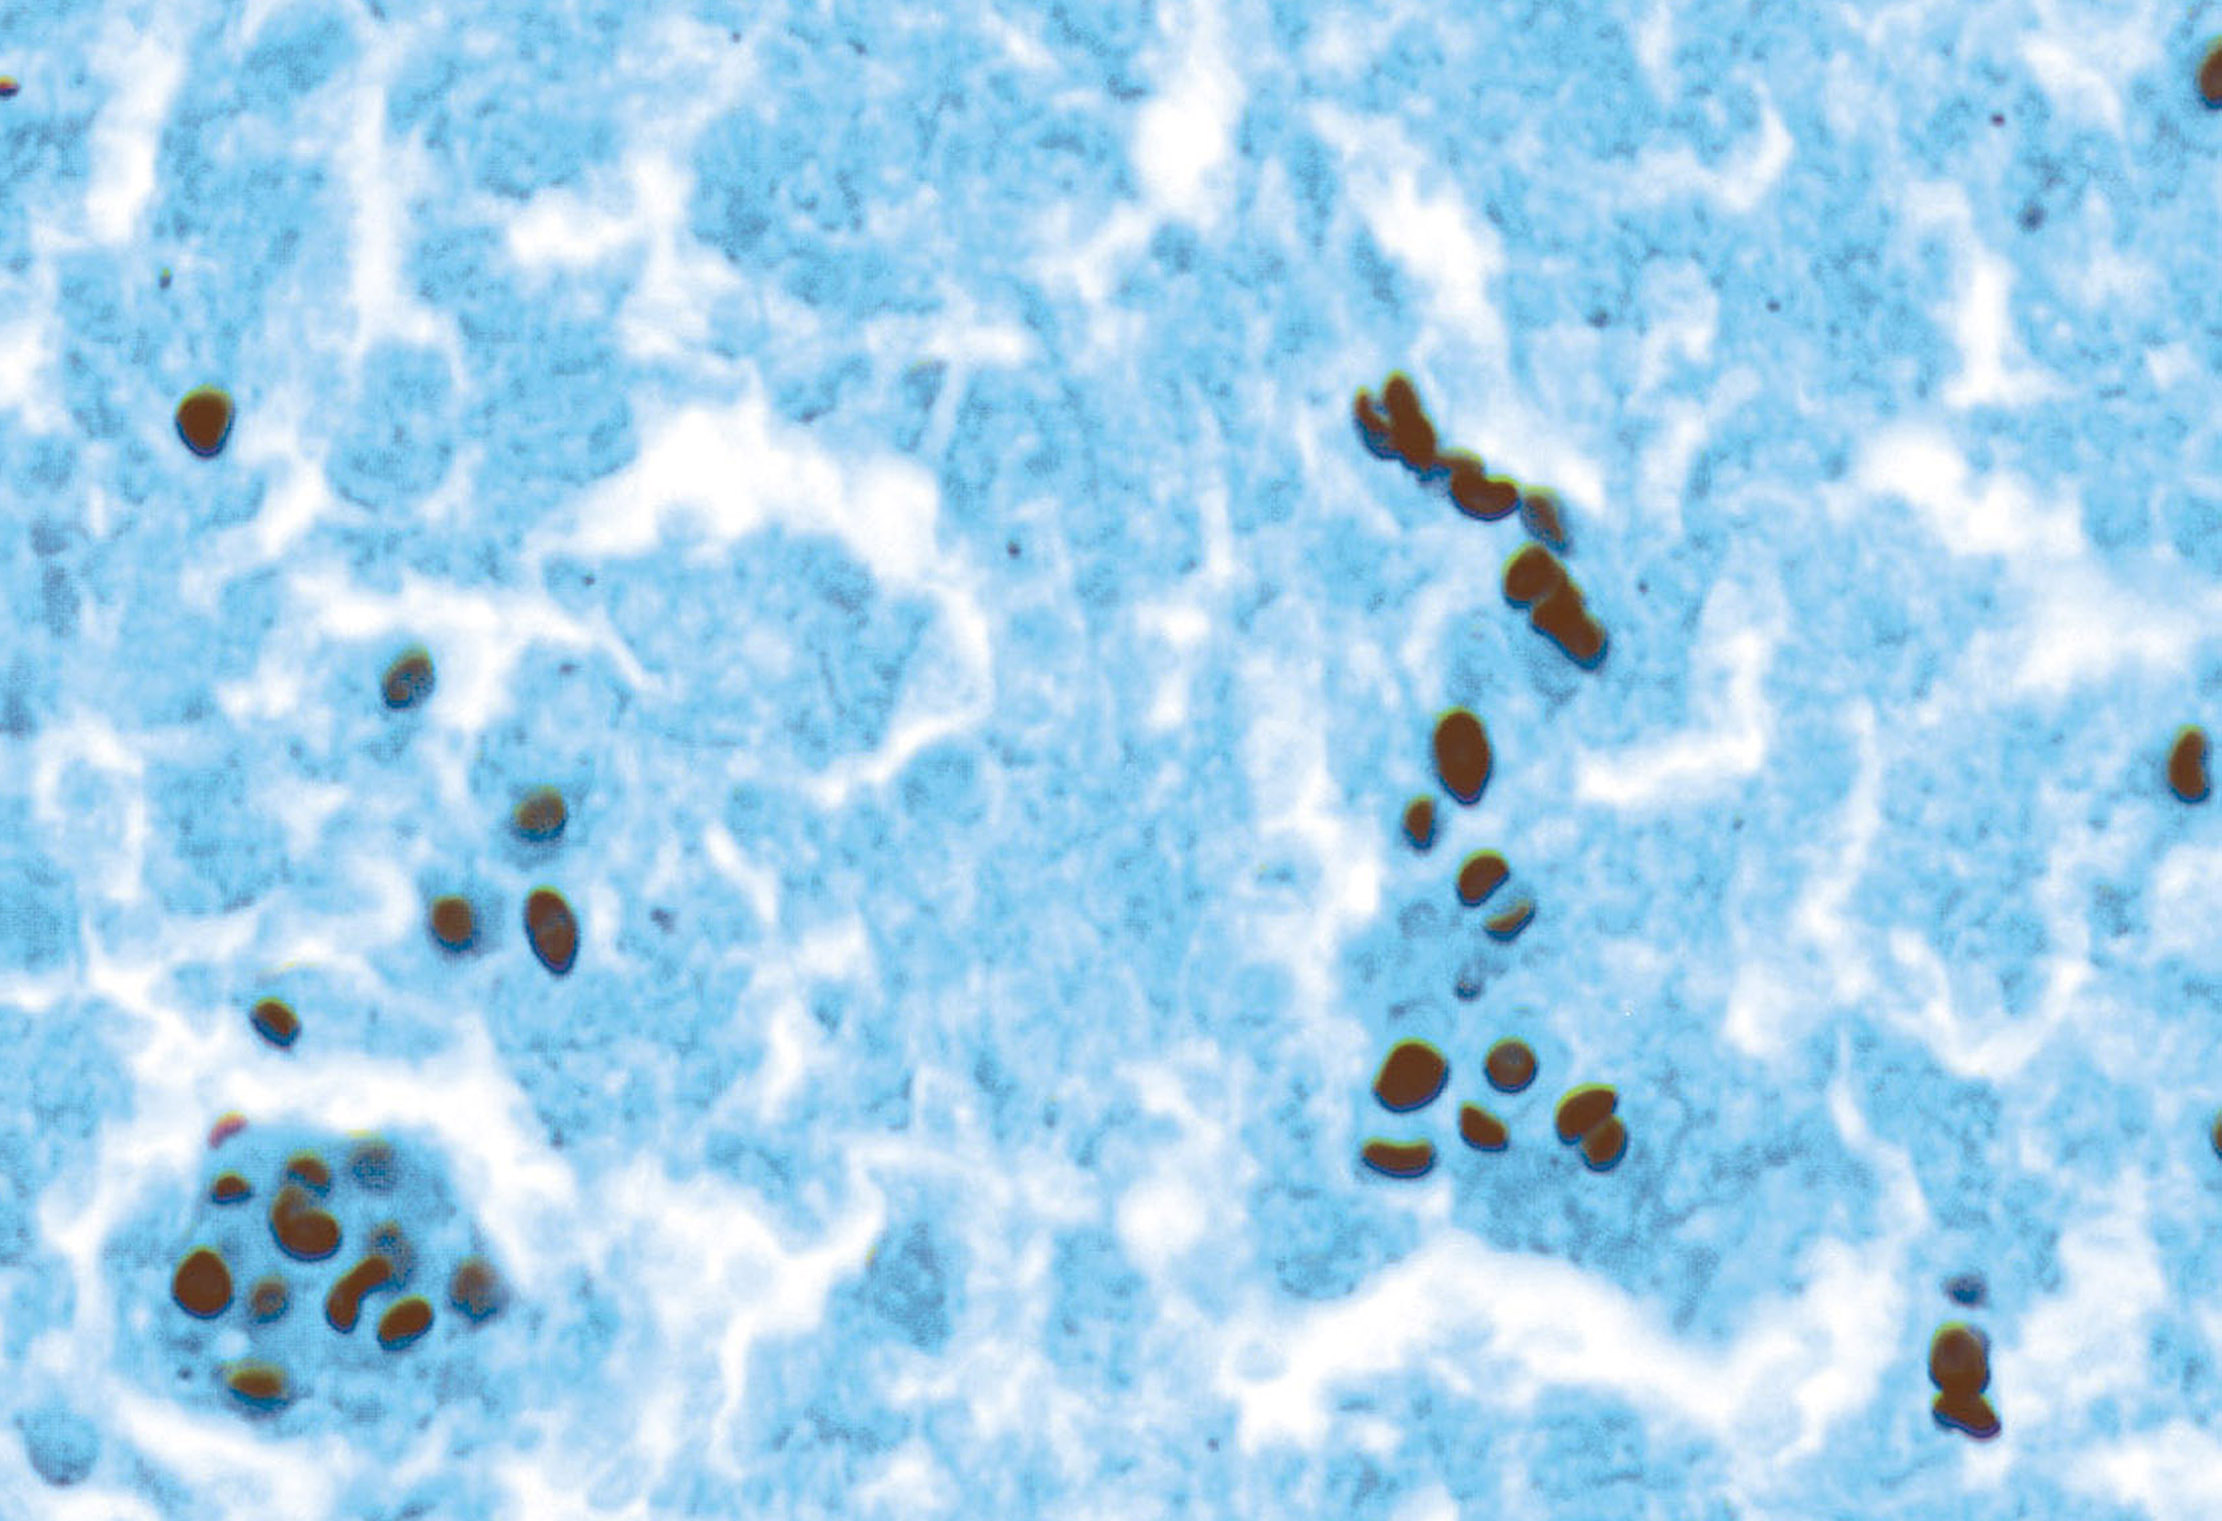

Microscopic (histologic) images

AFIP images

- Post vaccination bacille Calmette-Guerin infection occurs in 1% of infants, although swelling usually subsides (Braz J Med Biol Res 2004;37:697)BACILLARY ANGIOMATOSIS Left: Proliferated blood vessels are separated by abundant eosinophilic, vaguely fibrillary material. Some neutrophils are also seen. Right: Barely canalized blood vessels separated by eosinophilic interstitial materials in the absence of neutrophils.